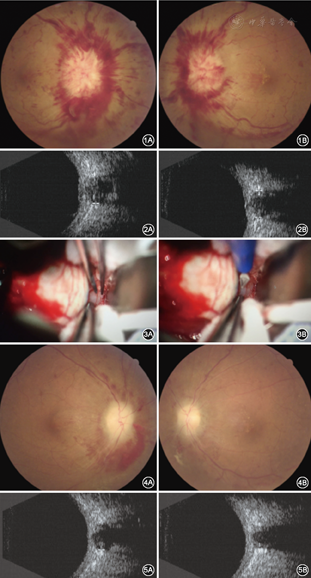

患者女性,48岁。因头痛伴双眼无痛性渐进性视力下降40 d、双眼视力下降加重20 d,于2016年6月24日至首都医科大学宣武医院眼科门诊就诊。40 d前患者因头痛伴恶心呕吐就诊于本院神经外科,行磁共振脑静脉窦血管成像,发现患者为先天性脑血管狭窄,造成颅内压升高,颅内压为300 mmHg(1 mmHg=0.133 kPa),20 d前出现双眼视力下降,不伴眼红眼胀,不伴视物变形及视物发暗,就诊于我院眼科,由门诊以双眼视乳头水肿收入院。既往体健,否认全身病及家族遗传史。入院后眼部检查:视力双眼无光感;眼压:右眼12 mmHg,左眼14 mmHg;双眼结膜轻充血,角膜透明,前房深,瞳孔中等大,直径4 mm,直接间接对光反射消失,双眼晶状体混浊。眼底:双眼视盘水肿,高达5 D,边界不清,视盘静脉迂曲扩张,可见双眼视盘周围浓密火焰状出血,视盘周边视网膜水肿,黄斑星芒状渗出(图1)。眼部B超可见双眼视神经增宽,鞘内可见液体(图2)。入院诊断为双眼视乳头水肿,先天性脑血管狭窄。入院后完善各项术前准备,于2016年6月27日在局部麻醉下行右眼视神经鞘减压术,术中充分暴露球后视神经,发现视神经增粗,视神经鞘内可见液体,划开增粗的视神经鞘,见脑脊液从视神经鞘内流出。手术顺利,术后给予左氧氟沙星滴眼液点术眼抗炎治疗,并给予营养神经药物治疗。术后1周眼部复查:视力:右眼光感,左眼无光感,眼压:右眼11 mmHg,左眼14 mmHg,右眼结膜充血,缝线在位,双眼角膜透明,前房深,瞳孔圆,直接间接对光反射迟钝,晶状体混浊,眼底:双眼视网膜红润,右视盘水肿较前明显减轻,边界欠情,动脉细,可见视盘周边视网膜水肿,少量火焰状放射状出血及渗出,黄斑可见渗出,左眼视盘水肿明显,边界不清,视盘静脉迂曲,周边可见火焰状出血。

为进一步治疗左眼视乳头水肿,缓解视神经鞘内脑脊液对左眼视神经的压力,患者由门诊于2016年7月8日以左眼视乳头水肿、右眼视神经鞘减压术后收入院,并于2016年7月11日在局麻下行左眼视神经鞘减压术,术中充分暴露球后视神经,发现视神经增粗,视神经鞘内可见液体,划开增粗的视神经鞘,见脑脊液从视神经鞘内流出(图3),手术顺利,术后给予左氧氟沙星滴眼液点术眼抗炎治疗,并给予营养神经药物治疗。左眼视神经鞘减压术后第1天、右眼视神经鞘减压术后2周复查视力:右眼手动/颞侧及鼻侧,左眼手动/眼前;眼压:右眼14 mmHg,左眼12 mmHg;双眼结膜充血,左眼结膜缝线在位,角膜透明,前房深,双眼晶状体混浊。术后眼底:双眼视盘色淡,边界欠清,右眼视盘周围视网膜轻度水肿,可见视盘上方及鼻下方片状出血,较术前明显好转,动脉细,黄斑少量渗出,左眼视盘色淡,视盘鼻下方可见少量线状出血及渗出,动脉静脉管径细,黄斑轻度渗出(图4)。术后患者眼部B超可见双眼视神经鞘内液体减少(图5)。